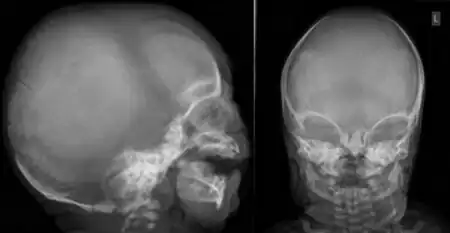

Oto-palato-digital syndrome is the generalised term for two conditions, oto-palato-digital syndrome type I (OPD1) and oto-palato-digital syndrome type II (OPD2), that are both X-linked recessive genetic disorders with overlapping phenotypes. The most severe phenotypes of each syndrome occur only in males, with females generally having attenuated forms of the condition, although this does not apply to all individual cases.[1] Some writers conceptualise oto-palato-digital syndrome as a spectrum disorder including two similarly-presenting genetic syndromes, frontometaphyseal dysplasia and Melnick-Needles syndrome.[2]

The conditions are characterised by skeletal abnormalities, cleft palate (a hole in the roof of the mouth), and hearing loss.[1] These symptoms are common to craniofacial syndromes as a whole.[3] Hand defects are particularly associated.[2] Of the conditions, OPD1 has the milder phenotype, with normal intelligence and modestly reduced stature.[2] In OPD2, the characteristic facial features are more severe and intellectual disability frequent; most OPD2 cases in males are stillborn or die during infancy.[1][2] As an X-linked recessive disorder, both forms are generally more severe in males, who have one X chromosome, than females, who have two.[4] Reports from patients of their experiences demonstrate a broad spectrum of symptom severity, including within families,[5] which has also been reported in the medical literature.[6]